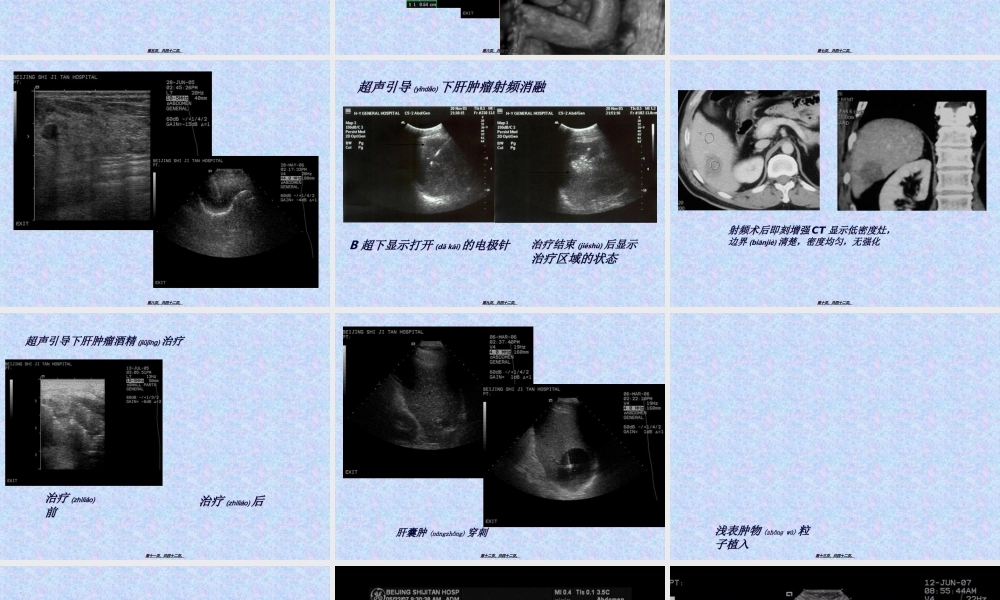

(fùbù)第一页,共四十二页。第一页,共四十二页。常用(chánɡyònɡ)概念•超声人耳可以接受的频率(pínlǜ)范围16~20000Hz,高于20000Hz者称为超声,常用的诊断超声频率2.5~7.5MHz。超声在人体内传播速度平均为1540m/s。•超声诊断利用超声波在人体组织内传播过程中,经过声反射等原理,将获得的信息加以分析综合,借以探索体内器官生理和病理变化,由此来判断疾病的一种诊断方法。第二页,共四十二页。第二页,共四十二页。超声诊断仪分类(fēnlèi)•A型:幅度(fúdù)调制型•B型:辉度调制型•M型:超声心动图•D型:ColorDopplerFlowImaging•三维超声第三页,共四十二页。第三页,共四十二页。回声描述(miáoshù)分类•无回声介质(jièzhì)均匀,内无界面反射,透声良好,主要用于含液性器官或病变。•低回声介质结构细,内部少界面反射,多见于实质而均匀的器官和病变。•强回声表明界面反射复杂,声阻大,见于含气体和钙盐的器官和病变。•声影表明界面声阻极大,使声能大量反射,形成强回声光团,其后方形成纵向条状暗带第四页,共四十二页。第四页,共四十二页。临床(línchuánɡ)应用范围颅脑、眼部、甲状腺、乳腺、心脏、肝脏、胆道、胰腺、脾、腹膜(fùmó)后、阑尾、泌尿系、妇科、产科、软组织、关节、血管等等第五页,共四十二页。第五页,共四十二页。第六页,共四十二页。第六页,共四十二页。介入性超声介入超声也称作超声引导靶向诊疗技术(InterventionalUltrasound),其主要(zhǔyào)特点是在实时超声的监视或引导下,完成各种穿刺活检、造影以及抽吸、插管、注药、消融等操作,是现代超声医学的主要(zhǔyào)分支,也是目前微创手术的方向之一。第七页,共四十二页。第七页,共四十二页。第八页,共四十二页。第八页,共四十二页。BB超下显示打开超下显示打开(dǎkāi)(dǎkāi)的电极针的电极针治疗结束治疗结束(jiéshù)(jiéshù)后显示后显示治疗区域的状态治疗区域的状态超声引导超声引导(yǐndǎo)(yǐndǎo)下肝肿瘤射频消融下肝肿瘤射频消融第九页,共四十二页。第九页,共四十二页。射频术后即刻增强射频术后即刻增强CTCT显示低密度灶,显示低密度灶,边界边界(biānjiè)(biānjiè)清楚,密度均匀,无强化清楚,密度均匀,无强化第十页,共四十二页。第十页,共四十二页。治疗治疗(zhìliáo)(zhìliáo)前前治疗治疗(zhìliáo)(zhìliáo)后后超声引导下肝肿瘤酒精超声引导下肝肿瘤酒精(jiǔjīng)(...